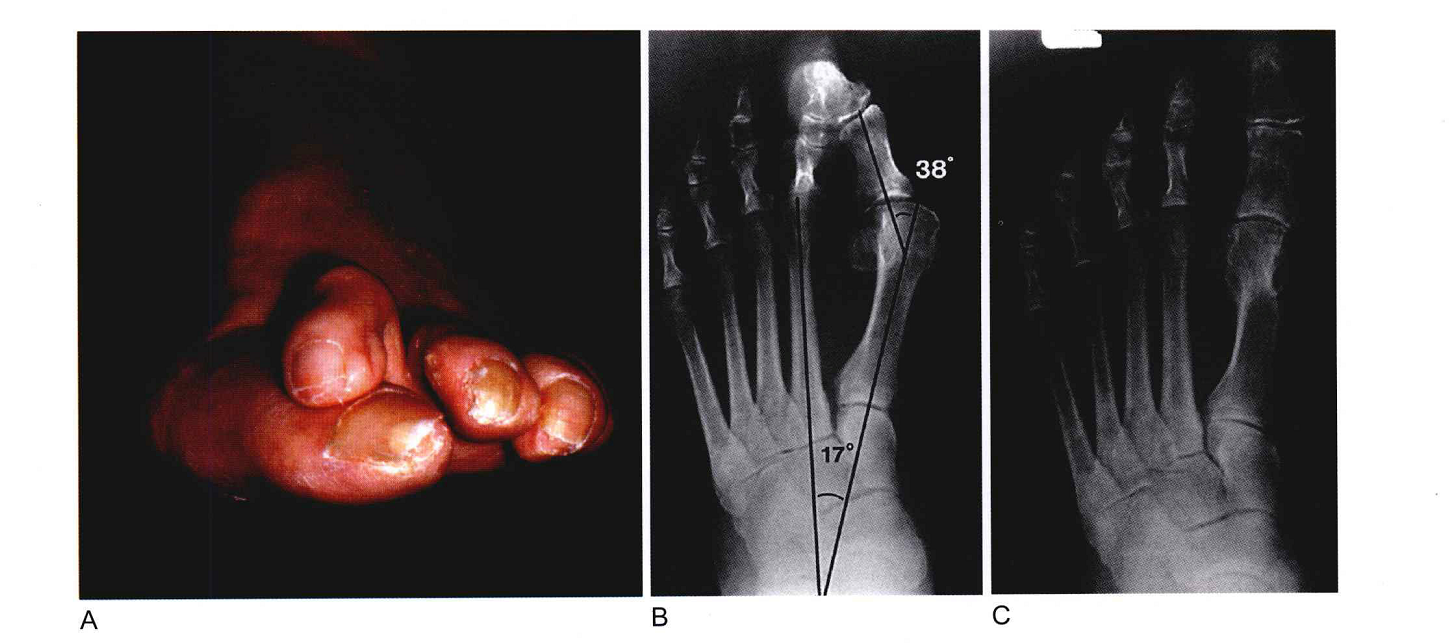

拇外翻即拇指向外倾斜。 约有一半病人有遗传史。拇外翻的症状表现为拇趾向外偏移,挤压第二趾头,使得第二趾抬高,位于拇趾之上,形成槌状趾。治疗拇外翻治疗方法也很重要

拇外翻的治疗方式包括保守治疗与手术治疗,对于早期病变者,疼痛较轻,可采用非手术疗 大拇趾外翻对成人而言是相当普遍的,对有拇指外翻症状疑虑者,应先至具有专业足部诊